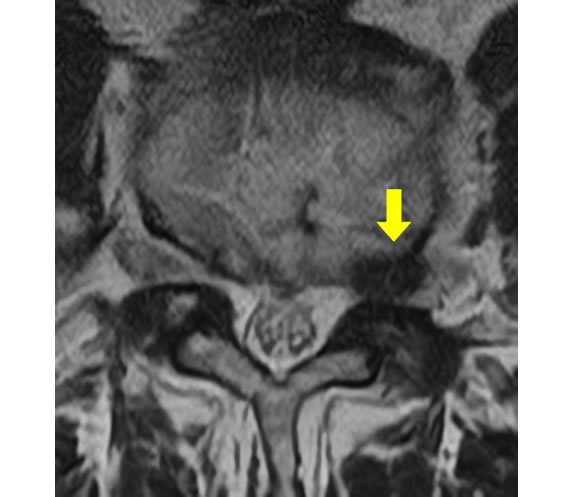

後方から内視鏡でアプローチする場合は椎弓の 間の 黄色靭帯、 および最低限の椎弓を切除して 、 内視鏡を進入させます。

(共に腰椎を輪切りした図)

ご高齢の方で、 骨の変形が強い場合は最低限の骨切除で椎間板、および靭帯を切除して、神経の圧迫を解除することもできます。

腰部脊柱管狭窄症術前

術後